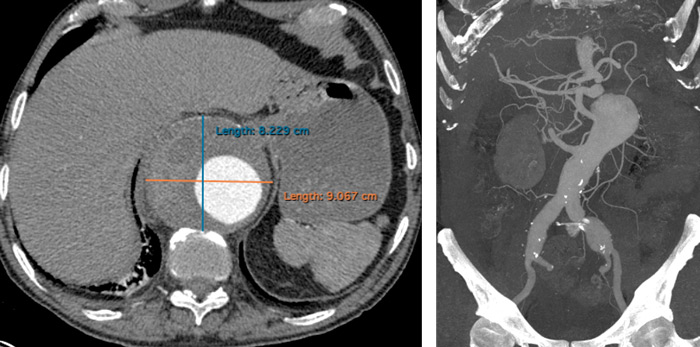

- Urgent CT scan: voluminous thoraco-abdominal aneurysm and bilateral iliac aneurysm

At CT scan control, 6 months after operation, the patient had a type-2 endoleak with enlargement of the aneurysmal sac.

- Type II endoleak (A);